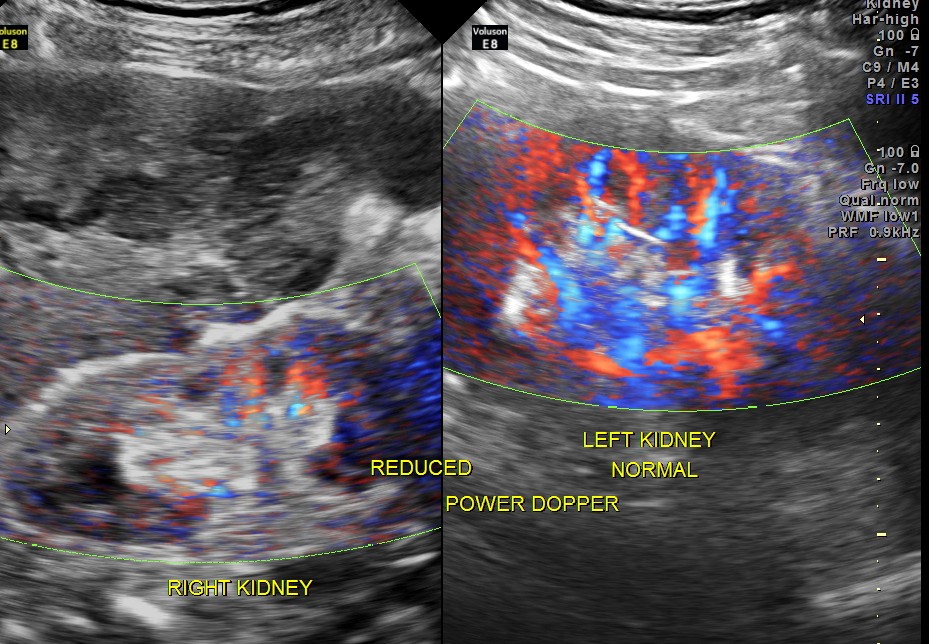

Clinically he had uncontrolled systemic hypertension and mildly elevated s. creatinine of 1.7 mgms/dl.

The diagnosis offered was multiple liver secondaries with incidental finding of shrunk right kidney with probable reduced function.